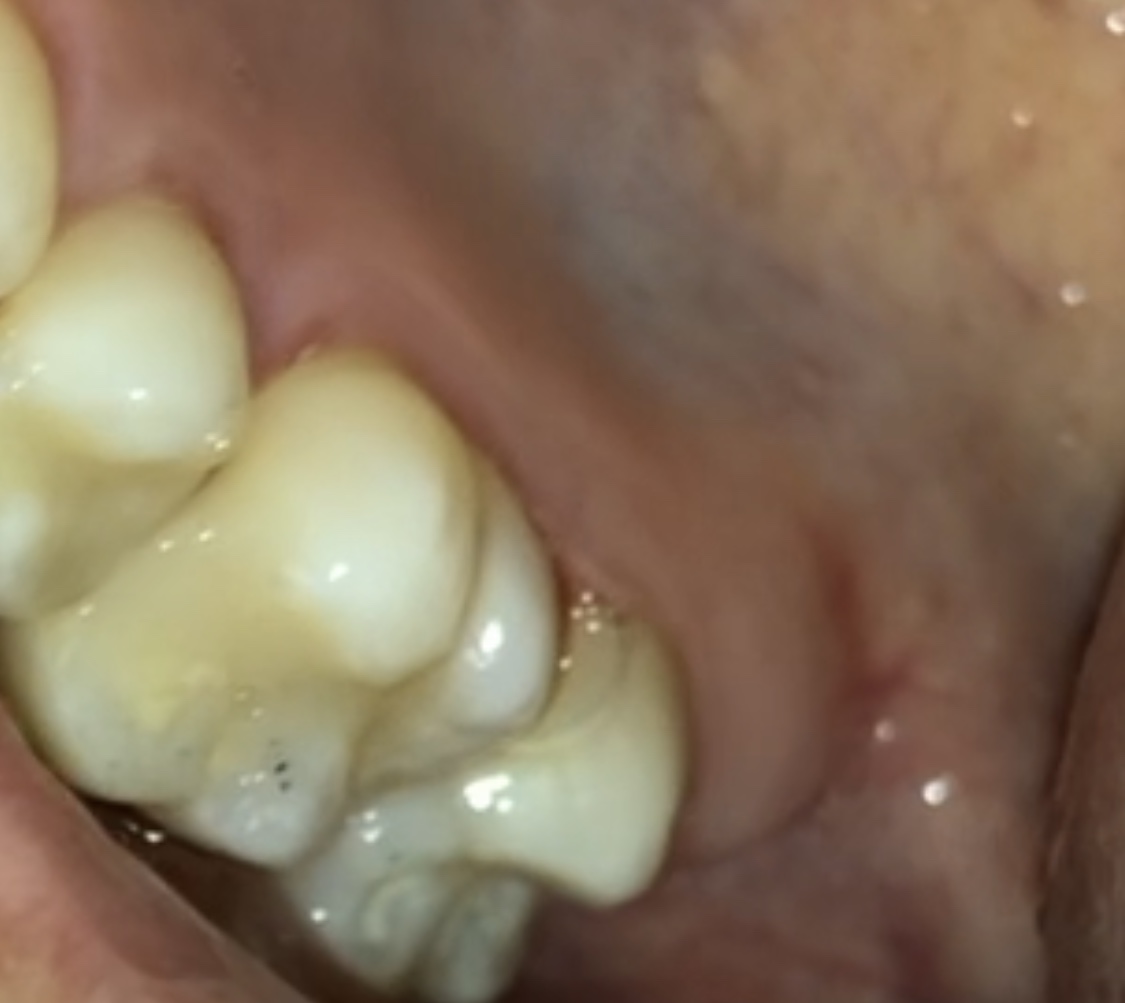

Vanmiddag heb ik een (diep) gaatje laten boren tussen/in een kies ergens achterin mijn bovengebit. Toen ik vlak na de behandeling naar de kies keek, zag ik wat grijze plekjes, maar deze zijn nu (grotendeels) weer wit. Kan dit een verkleurde vulling zijn, of is dit een reactie van mijn tand op de ingreep? Is dit normaal?

Ik heb een foto bijgevoegd! Eerst had ik dus die zwarte plekjes, en een paar uur later is dit wit.